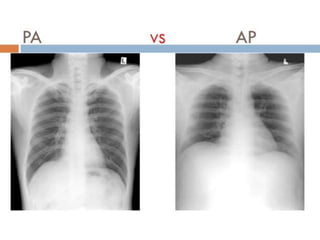

PA Film

Position : erect , supine , PA or AP